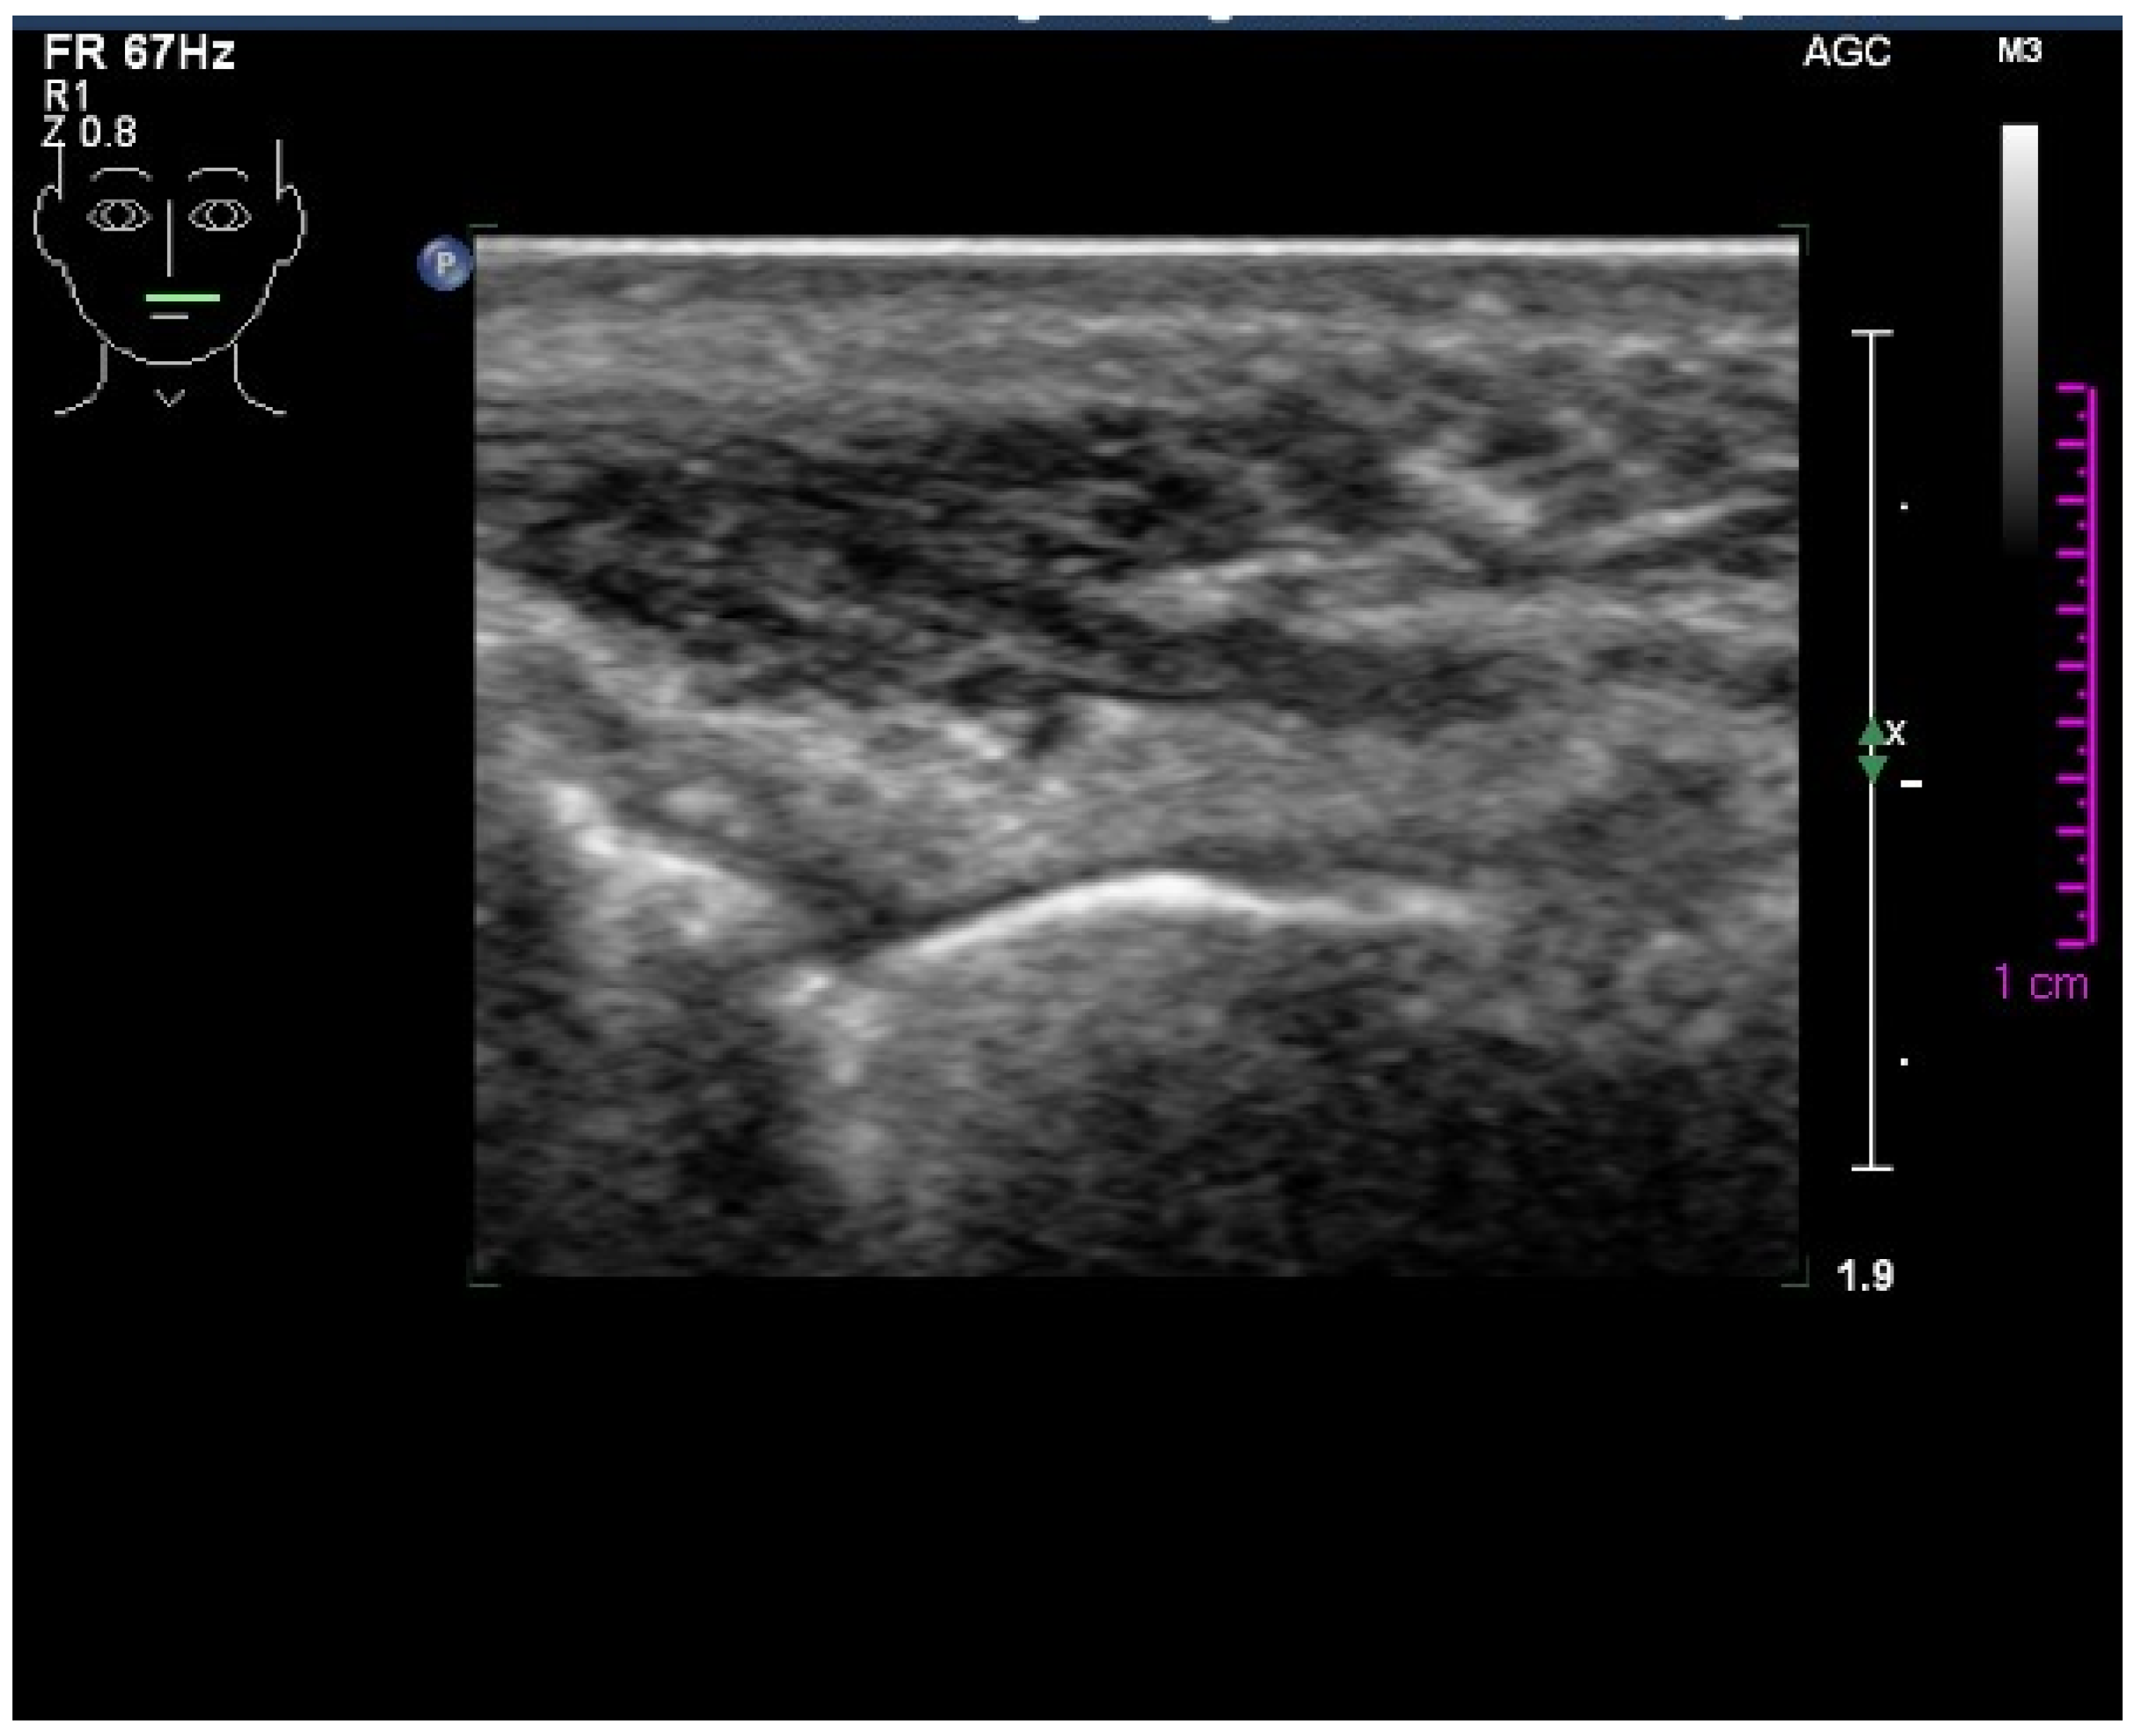

2.1. Case Report

3.1. Histological and Clinical Follow-Up